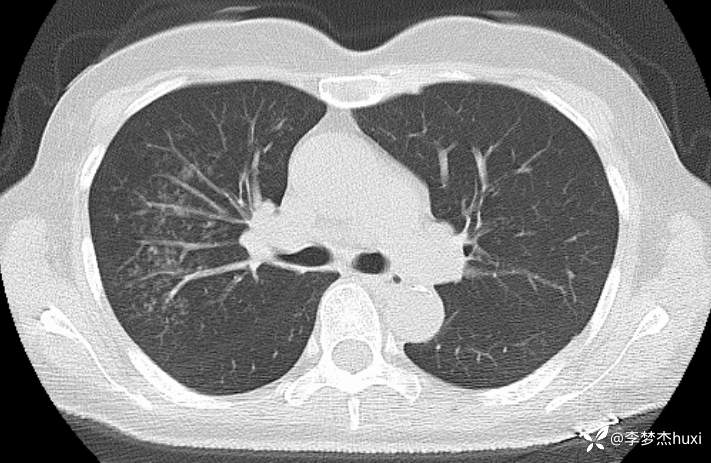

女性53岁,腮腺癌术后反复咳嗽、咳痰,胸部CT以树芽征为特点改变,最可能的是哪种疾病

【现病史及既往史】: 1.患者中年 女,患者于入院前5天无明显诱因出现咳嗽,咳痰,为黄绿色痰,量少,不易咳出,伴发热,最高体温不详,伴周身乏力,无胸痛,无呼吸困难,无恶心、呕吐,无腹痛、腹泻,无抽搐及意识障碍,院外未诊治,症状无好转,今患者及家属为进一步诊治前来我院就诊,门诊查胸部CT:右肺上叶占位性病变应考虑,右肺上叶空洞;右肺下叶占位?双肺炎症,支气管炎?右肺门淋巴结增大,双肺实性结节,纵隔结节,主动脉及冠状动脉钙化,右侧乳腺结节?建议结合超声,建议结合临床复查。门诊以“肺炎”收入院 。

2.既往高血压病史20余年,最高达180/?mmHg,目前口服“缬沙坦胶囊、硝苯地平控释片、酒石酸美托洛尔”等药物治疗,血压未监测;2008年因右侧腮腺腺样囊性癌于天津肿瘤医院行手术治疗,术后给予放化疗,2019年肿瘤原位复发,于北京大学口腔医院再次行手术治疗,2023-8发现肿瘤侵犯右耳道,目前口服仑伐替尼治疗约12个月;2023-11开始应用帕博利珠单抗注射液免疫治疗,患者右肺上叶占位,2024-7于沧州市中心医院行穿刺活检,病理:腺样囊性癌,2024-08于北京市某医院行“肺部射频消融术”;患者术后时常呛咳,否认“冠心病、糖尿病”病史,否认“肝炎”、“结核”等传染病史;否认外伤史,无输血史;否认食物、药物过敏史,预防接种史不详,系统回顾无特殊。。